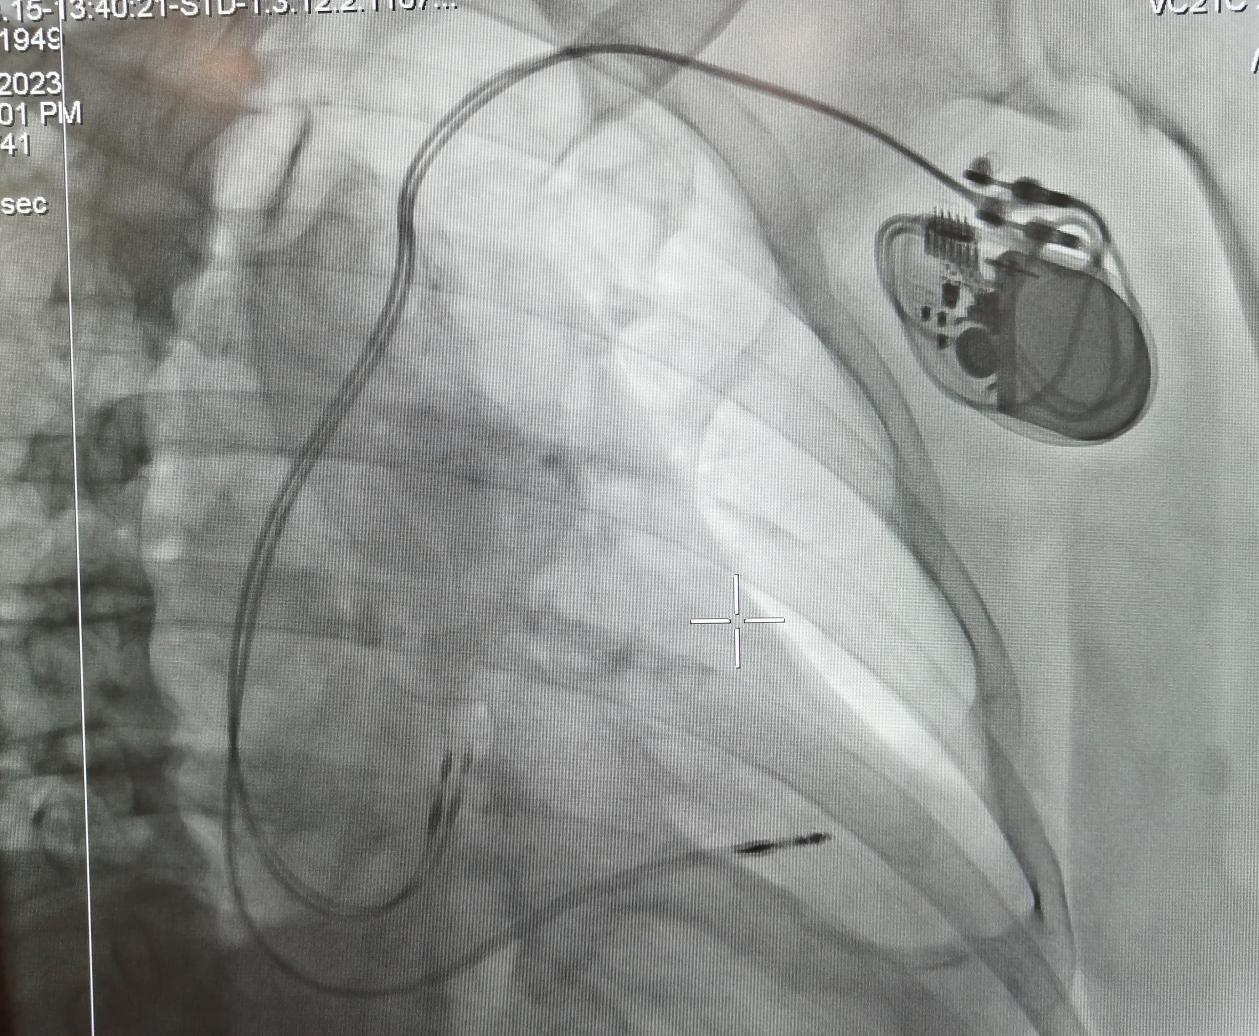

經(jīng)李慧新主任及科室團隊的會診,予以植入永久性起搏器,同時,李主任將患者的基本病情同白中樂教授進行了匯報,術(shù)前白教授詳細(xì)詢問患者的情況,為其制定了更精準(zhǔn)的治療方案,決定實施永久性起搏器(雙腔)植入術(shù)。8月15日中午,白教授帶領(lǐng)心血管內(nèi)科介入團隊成功為患者實施了“永久性起搏器(雙腔)植入術(shù)”。術(shù)后患者病情平穩(wěn),無頭暈不適。

起搏器植入后影像圖